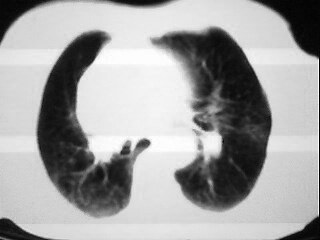

女,79,咳 嗽月余,无其它不适

1)两肺炎症。2)食管裂孔疝可能;建议行上消化道钡餐检查。